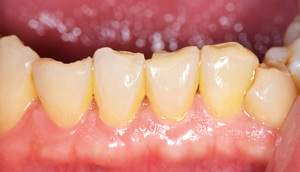

歯石除去

治療前

治療後

| 年齢 | 43歳・男性 |

| 主訴 | 歯石をとりたい |

| 治療内容 | 歯石除去 |

| 治療期間 | 30分 |

| 費用 | 約2,000円 |

| リスク・副作用 | ・歯ぐきの炎症が強いと歯石を取る際に出血することがあります ・処置後に歯がしみることがあります ・歯と歯の間に隙間ができるので、息が漏れ発音しにくいと感じることがあります ・歯ぐきの炎症が軽減すると歯ぐきが引き締まり、歯が長く見えることがあります |